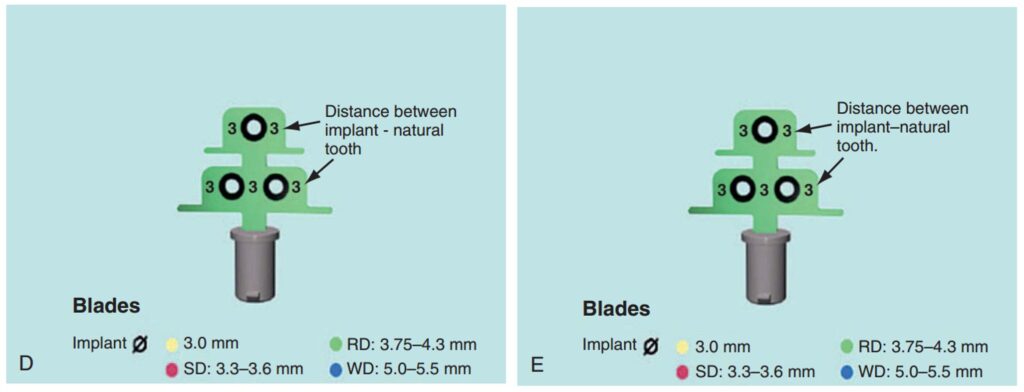

Dụng cụ hướng dẫn định vị Implant

Giúp xác định đúng vị trí đặt Implant và lựa chọn đường kính Implant tối ưu nhất (H2.18). Bộ hướng dẫn ITT gồm có:

– Tấm Titan, giúp hướng dẫn đường kính và vị trí của 1 – 2 Implant.

– Pin đo đạc có phần mở rộng, giúp hướng dẫn đường kính và vị trí Implant ở bệnh nhân không răng.

– Pin song song, để xác định độ song song của Implant.

– Cán của tấm Titan, giúp cầm nắm và đặt tấm Titan vào trong miệng 1 cách an toàn.